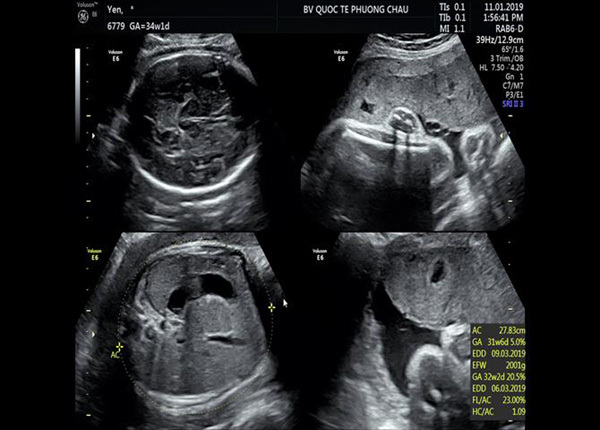

Từ kết luận của bác sĩ siêu âm về một trường hợp thai chậm tăng trưởng nặng, dây rốn quấn cổ 3 vòng - dây rốn thắt nút... sản phụ được chỉ định nhập viện với chẩn đoán: thai 34 tuần 01 ngày, ngôi đầu, chưa chuyển dạ/thai chậm tăng trưởng trong tử cung/dây rốn quấn cổ 3 vòng/theo dõi dây rốn thắt nút…

Bác sĩ Sản khoa Phương Châu cùng các chuyên gia đã tiên lượng và đánh giá tình trạng sức khỏe của sản phụ và quyết định chấm dứt thai kì ở tuổi thai 34 tuần 2 ngày để đảm an toàn cho bé.